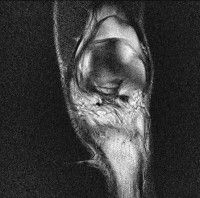

무릎 mri 간단히 봐주실 수 있으시나요 ㅠㅠ

안녕하세요 8년전 십자인대 수술하고 최근 무리한 운동에 무릎 불편감이 생겨서

mri 찍었습니다.

진단결과는 첫 찍은 병원에서 활액막염 이라는 진단을 받았습니다. 혹시 봐주실 수 있으실까요?

올라온 MRI가 단편적이라서 정확한 진단에 어려움이 있지만 십자인대에는 큰 이상이 있지는 않은것 같으며, 무릎관절내 물이 있는 것으로 보아 활액막염의 진단이 맞을 것 같습니다.

하지만 단편적인 영상이기 때문에 촬영병원에서 정확한 판독지 등을 받으시는 것이 좋겠습니다.